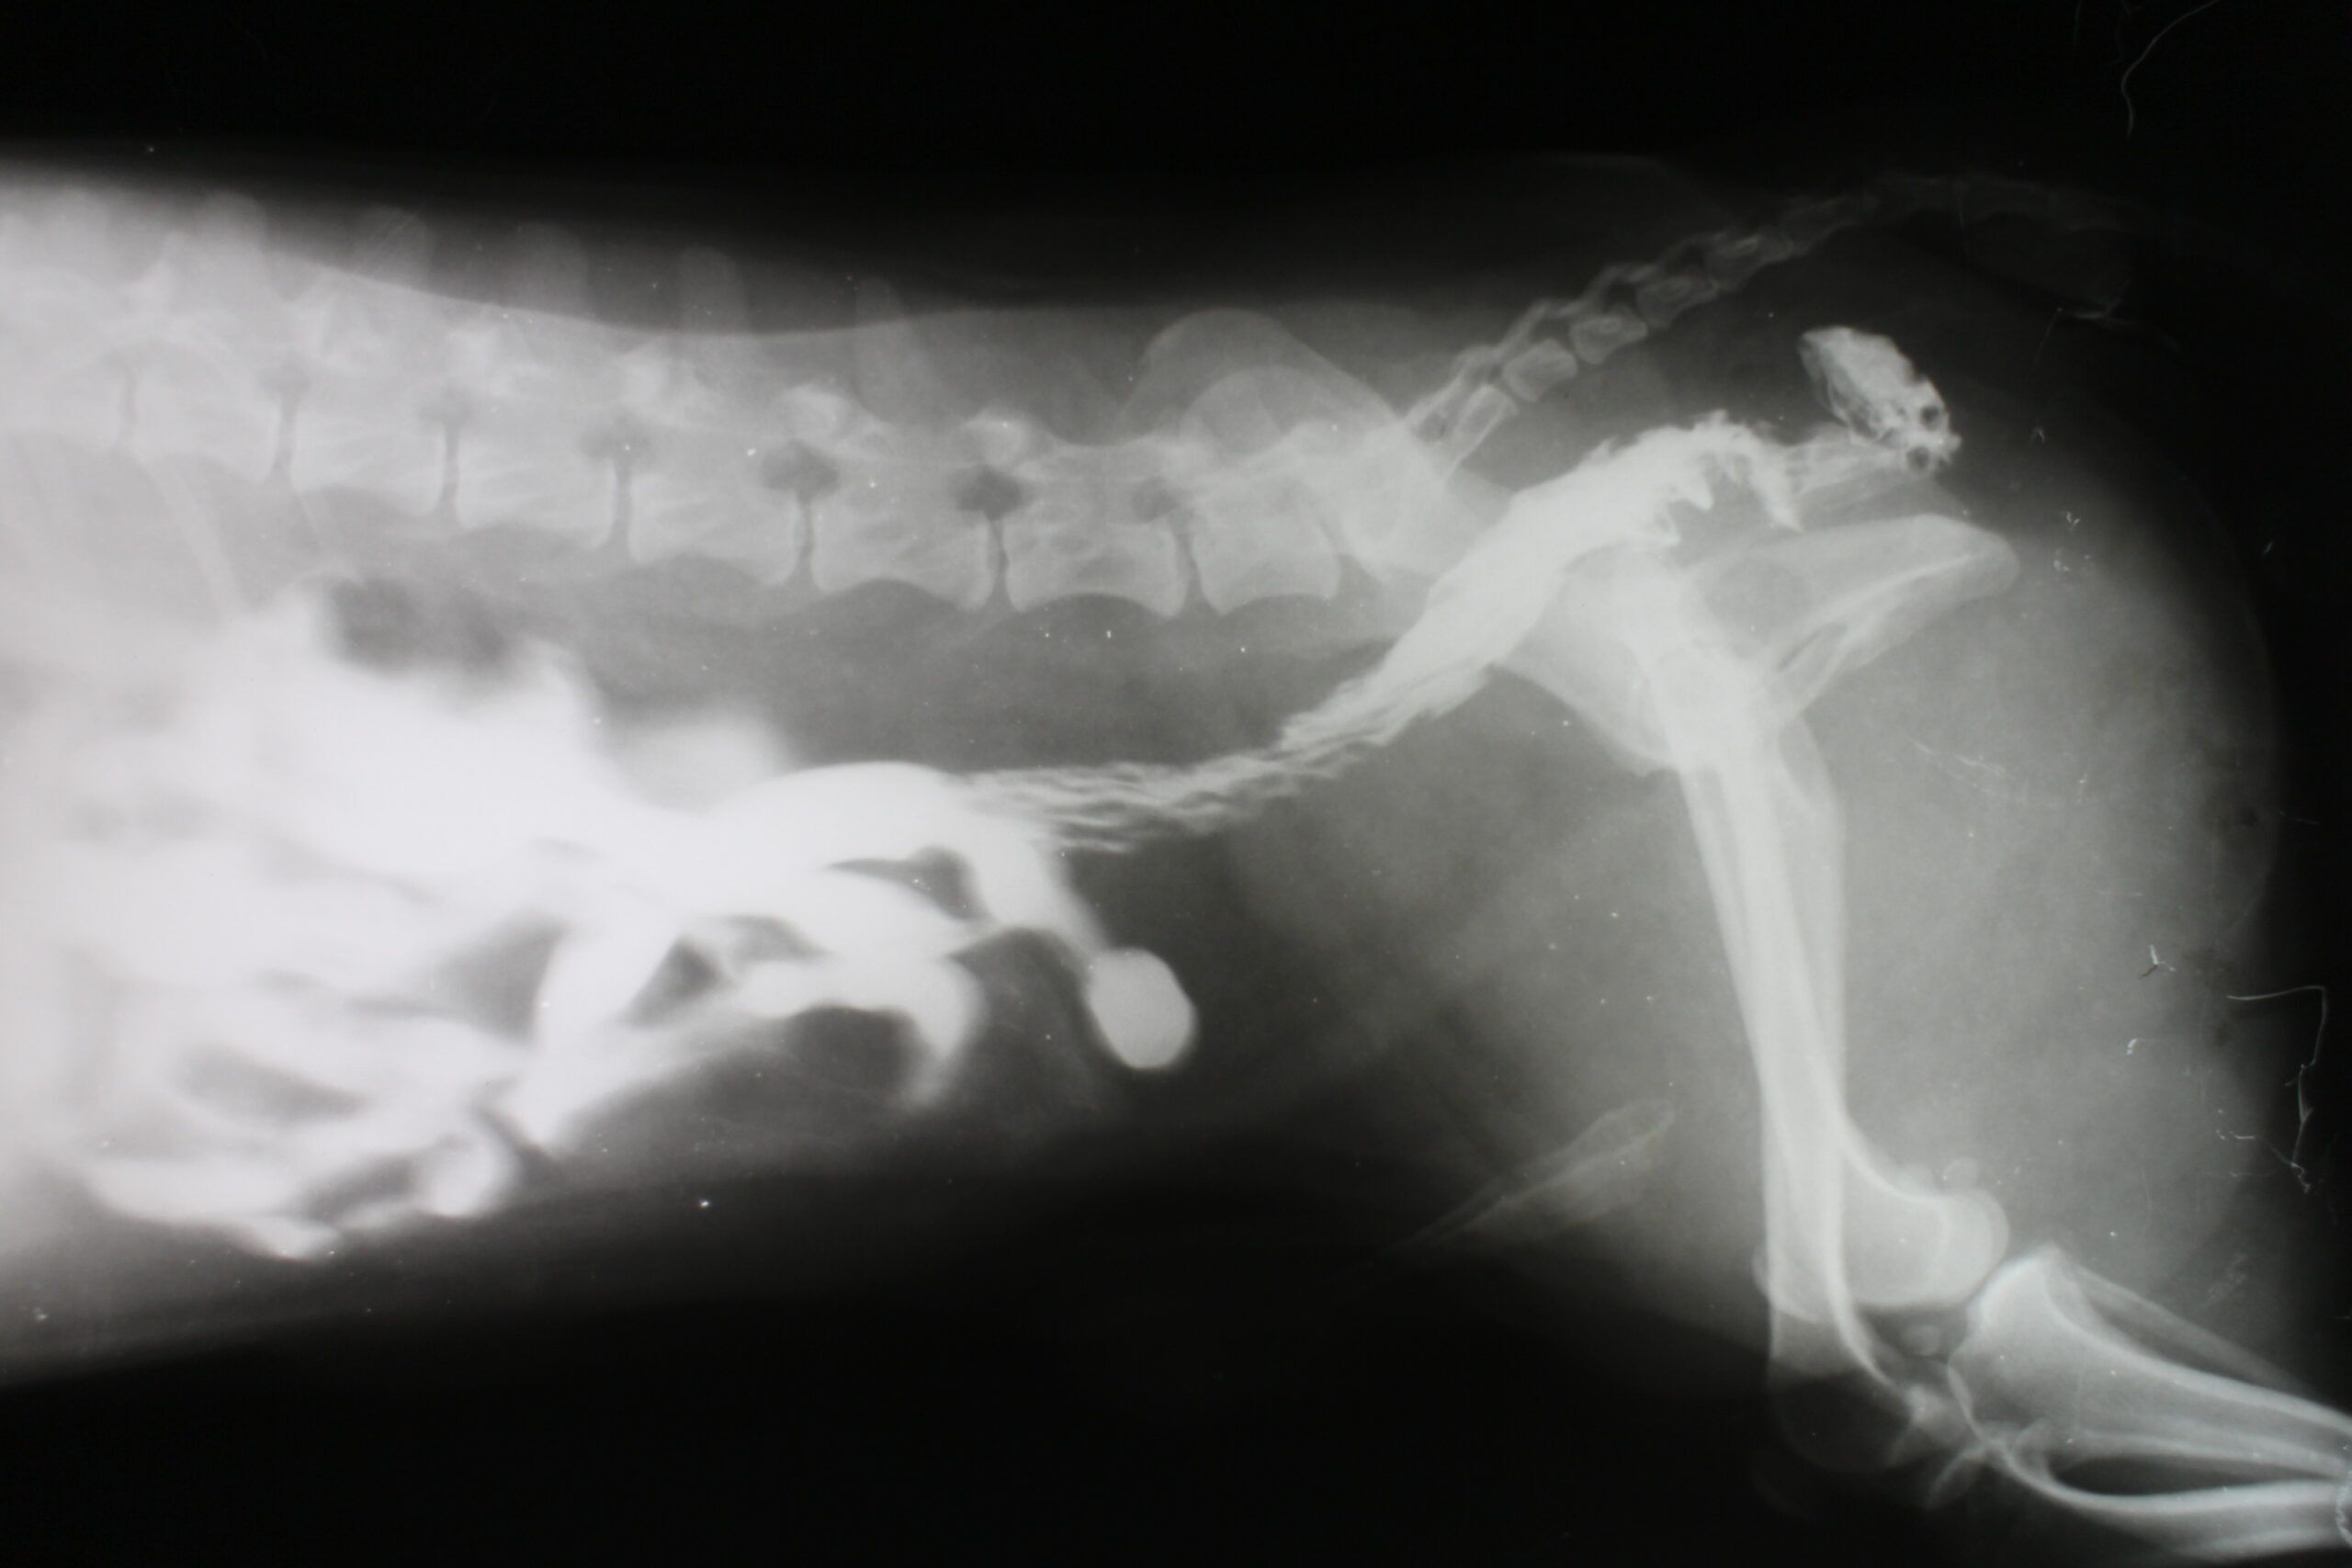

• Radiographs. X-rays on their own can’t diagnose bladder cancer. The main use of radiography is to determine if there is cancer spread to the bones. Chest x-rays are used to check for metastasis in the lungs.